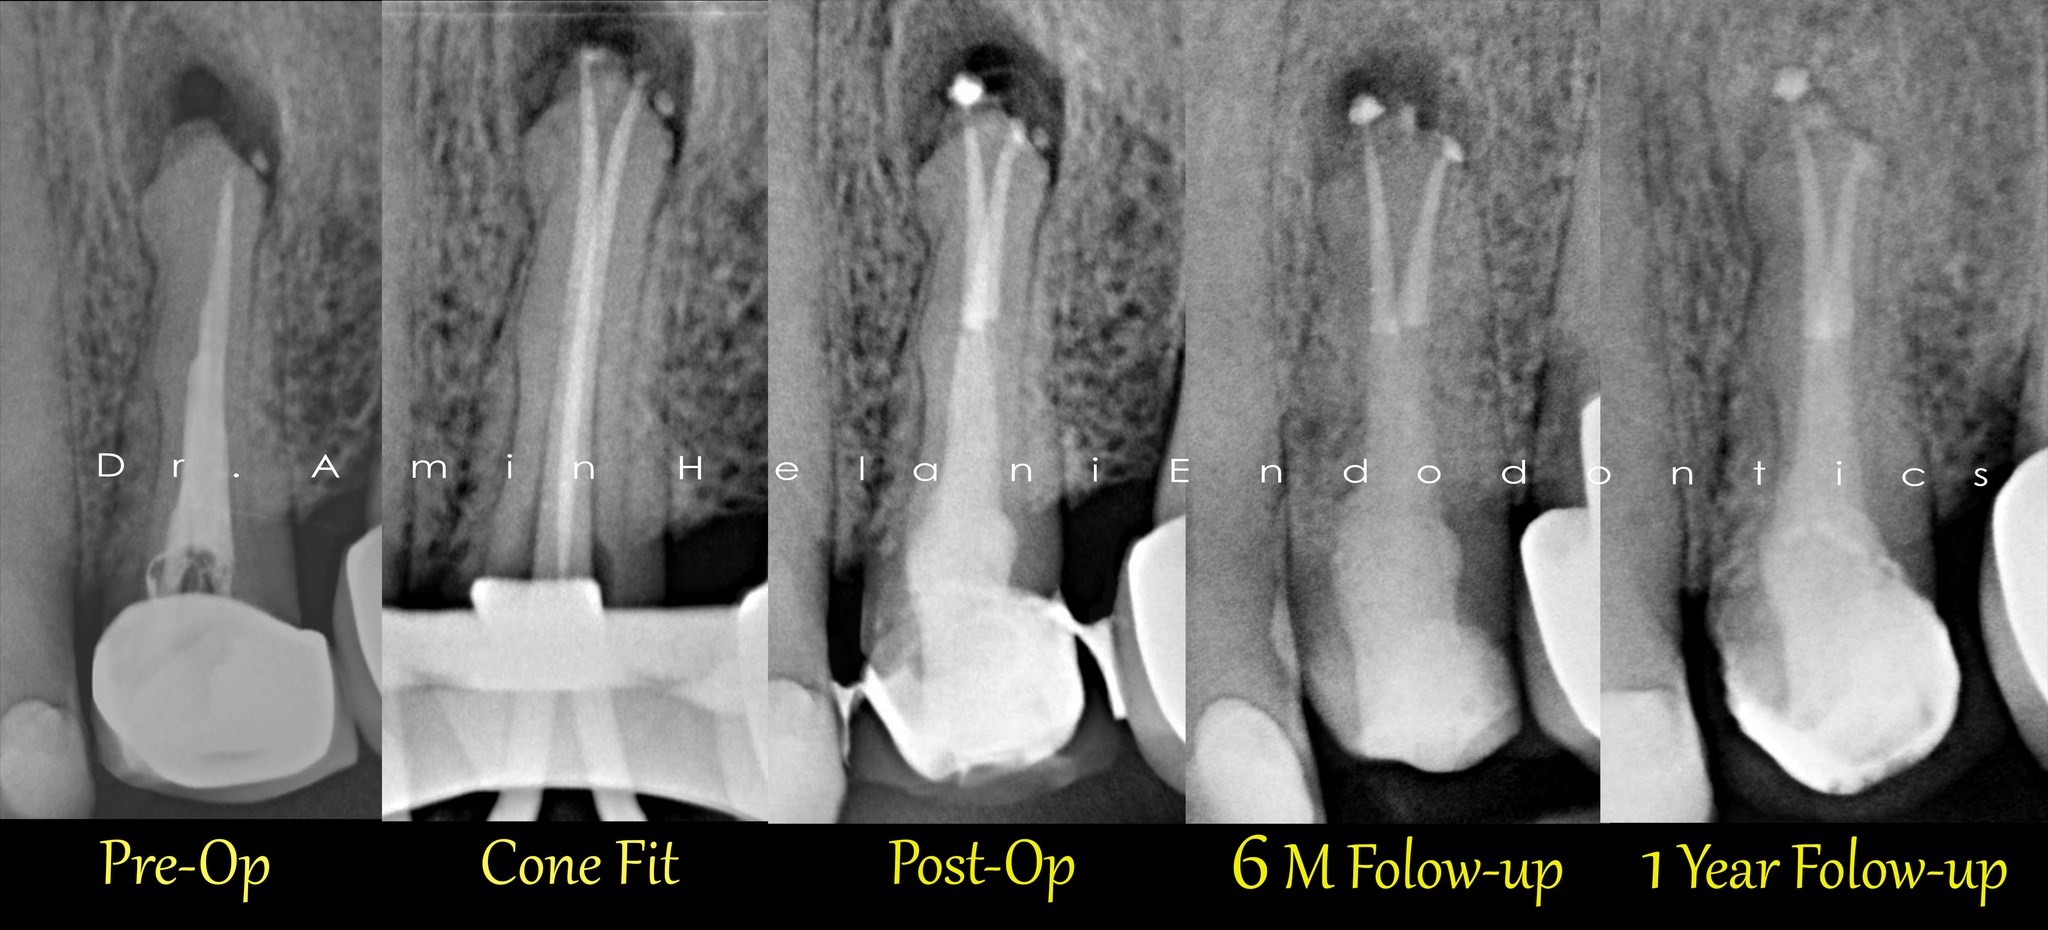

Entfernung eines abgebrochenen Instruments